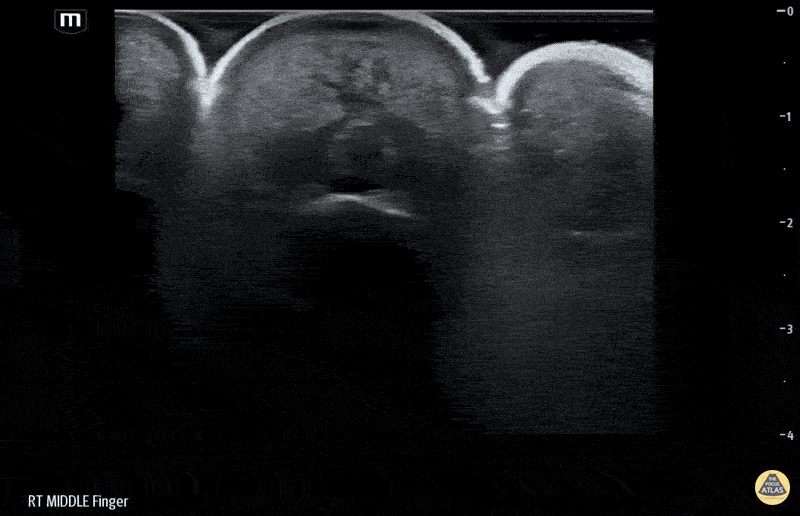

Musculoskeletal - Flexor Tenosynovitis Waterbath Ultrasound - Short axis

50 yo M presented to the ED after accidentally injuring his middle finger while welding, with reported fevers, finger swelling and all 4 Kanavel signs. Waterbath ultrasound shows fluid along the flexor tendon sheath extending distally. Hand consulted, patient taken to operative room for septic FTS. Erick Otiniano, MD MPH | DHREM PGY1 Fred Milgrim, MD | Director of Residency Ultrasound Education, Denver Health